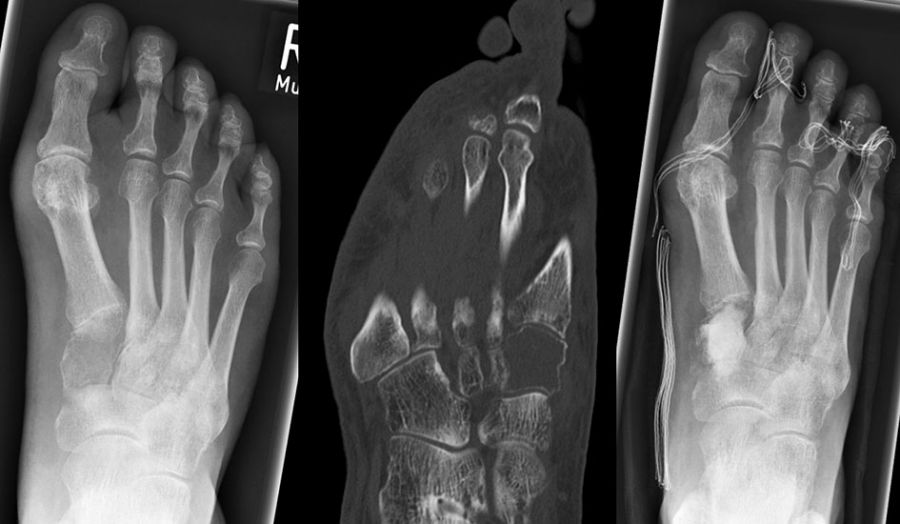

Das primäre, konventionelle Chondrosarkom des Fußes, welches nicht sekundär aus einem Enchondrom oder einer Exostose (exophytäres bzw. exostotisches Chondroarkom) sondern de novo entsteht, zeigt, ähnlich wie das Enchondrom, eine Prädilektion für die kurzen Röhren­knochen (Abb. 19). Das durchschnittliche Alter liegt hier bei 52 Jahren mit einer Bevorzugung des männlichen Geschlechts. In Abhängigkeit der Lokalisation und Graduierung des Tumors umfasst die geeignete operative Therapie die intraläsionale Curettage (G1) bis hin zur Amputation (G3) 34. Das Chondrosarkom ist nicht Strahlen- oder Chemotherapie-sensibel. Eine vollständige chirurgische Resektion bleibt deshalb die einzig sinnvolle Therapiemöglichkeit.

Das Chondrosarkom des Fußes zeigt, ähnlich wie das Enchondrom, eine Prädilektion für die kurzen Röhrenknochen. Das durchschnittliche Alter liegt hier bei 52 Jahren mit einer Bevor­zugung des männlichen Geschlechts. In Abhängigkeit der Lokalisation und Graduierung des Tumors umfasst die geeignete operative Therapie die intraläsionale Curettage (G1) (Abb.19) bis hin zur Amputation (G3) (Abb.10) 34.